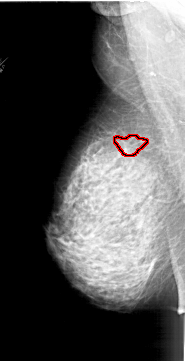

A_1878_1.LEFT_MLO

LEFT_MLO LINES 6496 PIXELS_PER_LINE 3316 BITS_PER_PIXEL 12 RESOLUTION 43.5 OVERLAY

FILE: A_1878_1.LEFT_MLO.OVERLAY

TOTAL_ABNORMALITIES 1

ABNORMALITY 1

LESION_TYPE MASS SHAPE IRREGULAR MARGINS SPICULATED

ASSESSMENT 4

SUBTLETY 1

PATHOLOGY BENIGN

TOTAL_OUTLINES 1

BOUNDARY